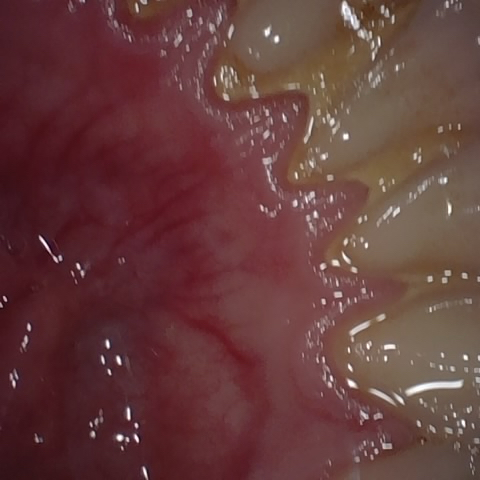

Annotated as "Good"